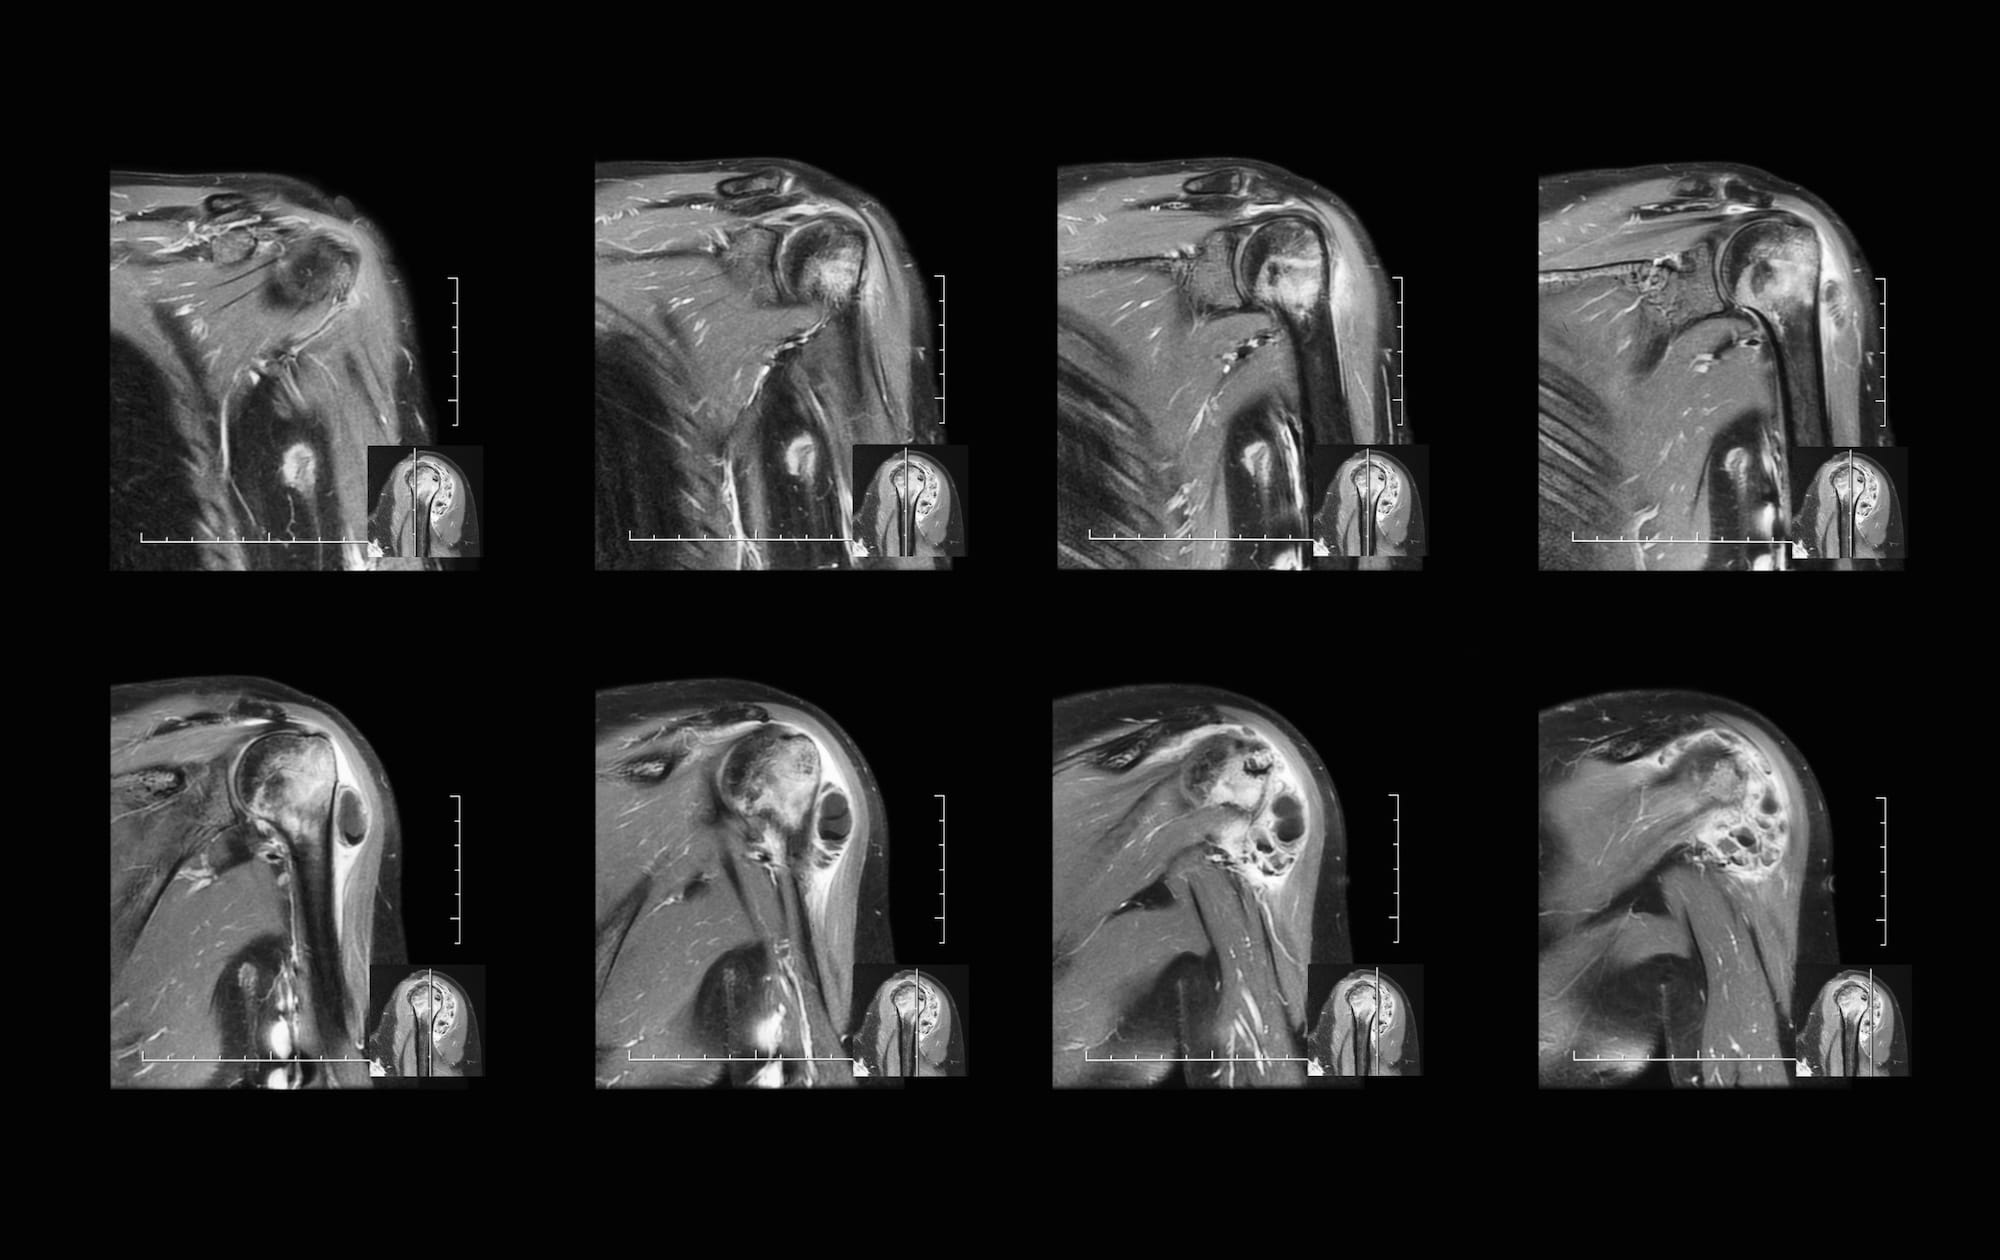

MR arthrogram (T2weighted fatsuppressed sequence) of a right hip in

MR arthrogram (T2weighted fatsuppressed sequence) of a right hip in What Is A Mri Arthrogram Hip  This article describes the technique for performance and interpretation of magnetic resonance arthrography of the hip. A hip arthrogram is a procedure where contrast is injected into the hip joint before a ct or mri. Magnetic resonance imaging (mri) of the hip uses a powerful magnetic field, radio waves, and a computer to produce detailed pictures of the. Mri arthrography. What Is A Mri Arthrogram Hip.